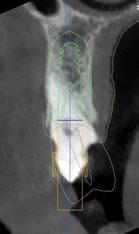

A tenor del estado oral proponemos múltiples opciones terapéuticas, consensuando entre paciente y facultativos una rehabilitación implantoprotésica fija superior e inferior. Debido a la lejanía de la residencia de la paciente, y motivados por las necesidades estéticas que esta exige, consideramos realizar una carga inmediata impresa con resina definitiva el mismo día de la cirugía. Tras el escaneado intraoral con el escáner Dexis IS3700 (Figuras 7 y 8) y realización de CBCT, subimos los ficheros a la plataforma Bego Guide,

procediendo a realizar una solicitud de encargo a través de un formulario. Antes de 72 horas recibimos una propuesta terapéutica. En ella se facilitan vistas 3D detalladas, así como valoraciones y consideraciones a tener en cuenta durante el fresado y la inserción de los implantes (Figuras 9 a 19). Decidimos realizar extracción de todas las piezas remanentes, dada su nula viabilidad a corto-medio plazo y en Bego (a través del portal) proponen mantener 3 piezas (las más viables técnicamente) en cada arcada para proporcionar el anclaje óptimo de la

Figura 10. Propuesta de planificación maxilar con encerado diagnóstico digital. Destaca la angulación del implante 1.6 esquivando el seno maxilar con un ángulo de inserción de 30 º y una emergencia protésica verticalizada.

16. Superposición radiológica implante 45 angulado, teniendo en consideración el encerado diagnóstico y preservando estructuras nerviosas.